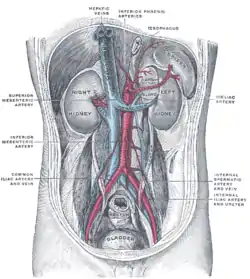

Section of the spleen, showing the termination of the small bloodvessels. Posterior abdominal wall, after removal of the peritoneum, showing kidneys, suprarenal capsules, and great vessels.

Posterior abdominal wall, after removal of the peritoneum, showing kidneys, suprarenal capsules, and great vessels. Arteries and veins around the pancreas and spleen.